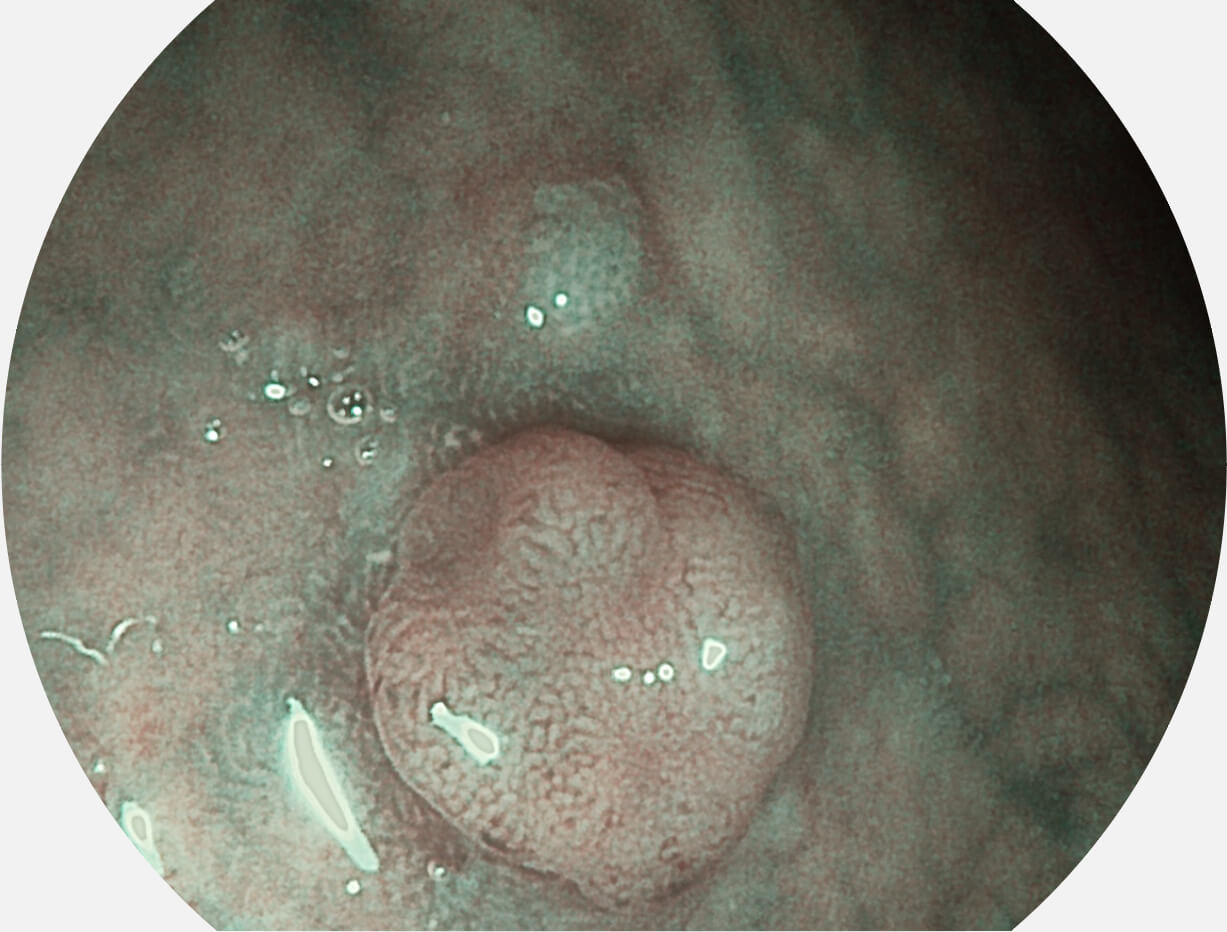

图像具有高亮度、高黏膜血管颜色对比度的特点,且不改变粘液、食物残渣、粪便的基本颜色,可在中远景下进行观察,助力消化道早期疾病的诊断。

采用光路合束技术,光谱自由度高,实现了更丰富的照明模式,染色模式SFI及VIST,从远景到近景,助力消化道早期疾病诊断。